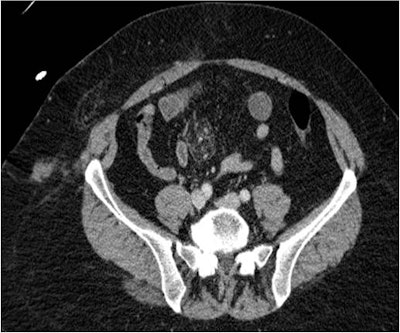

"Most of the injuries were to be expected, but we did observe two unusual ones in the aftermath of the train derailment -- an ileal mesenteric contusion and a posterior sternoclavicular dislocation," Bhattacharya said. "Fortunately, both patients recovered well."

Above, 51-year-old woman with mesenteric contusion. Axial contrast-enhanced CT image of the abdomen shows ileal mesenteric contusion. Note soft-tissue contusion as well. Below, 68-year-old woman with posterior sternoclavicular joint dislocation. Sagittal CT of the chest at bone windows demonstrates posterior sternoclavicular dislocation, with the medial clavicle in close proximity to the great vessels but not in contact. Images courtesy of Anup Bhattacharya.Bhattacharya and colleagues hope their findings will help their emergency physician peers better care for patients in the aftermath of accidents or disasters.